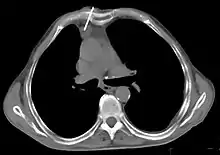

Le scanner thoracique est plus précis que la radiographie thoracique dans le diagnostic des thymomes, en raison d'une plus grande sensibilité envers les masses médiastinales. L'injection de produit de contraste iodé n'est pas forcément nécessaire, mais permet de préciser les rapports du thymome avec les structures vasculaires. Ceci permet à la fois la stadification et de préciser la stratégie chirurgicale lorsqu'elle est envisagée[28].

Les thymomes se présentent comme une masse bien définie du médiastin antérieur, proche du péricarde et dans un plan plus antérieur que les gros vaisseaux intrathoraciques (aorte ascendante et sa crosse, artère pulmonaire, veine cave supérieure). La masse peut être sphérique ou lobulée, mais présente un aspect homogène (plus rarement kystique) qui se réhausse après injection et peut contenir des calcifications[29].

Les critères scanographiques d'envahissement local doivent être recherchés car ils guideront le traitement. D'autre part, l'envahissement scanographique est corrélé au pronostic[30]. L'absence d'un liseré graisseux entre la masse et les vaisseaux, notamment l'aorte et la veine cave supérieure, est un signe d'envahissement local. L'ascension d'une coupole diaphragmatique, comme en radiographie thoracique, est un signe d'envahissement du nerf phrénique[31].

Scanner injecté, en fenêtre médiastinale, montrant un carcinome thymique envahissant les structures médiastinales :

1 : tumeur hétérogène, aux contours irréguliers, présentant des plages hémorragiques ;

2 : veine cave supérieure ;

3 : tronc artériel brachiocéphalique ;

4 : artères sous-clavière gauche et carotide commune gauche ;

5 : crosse de l'aorte ;

6 : sternum.